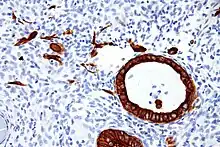

Keratin intermediate filaments in epithelial cells (red stain).

Cytokeratins are keratin proteins found in the intracytoplasmic cytoskeleton of epithelial tissue. They are an important component of intermediate filaments, which help cells resist mechanical stress.[1] Expression of these cytokeratins within epithelial cells is largely specific to particular organs or tissues. Thus they are used clinically to identify the cell of origin of various human tumors.